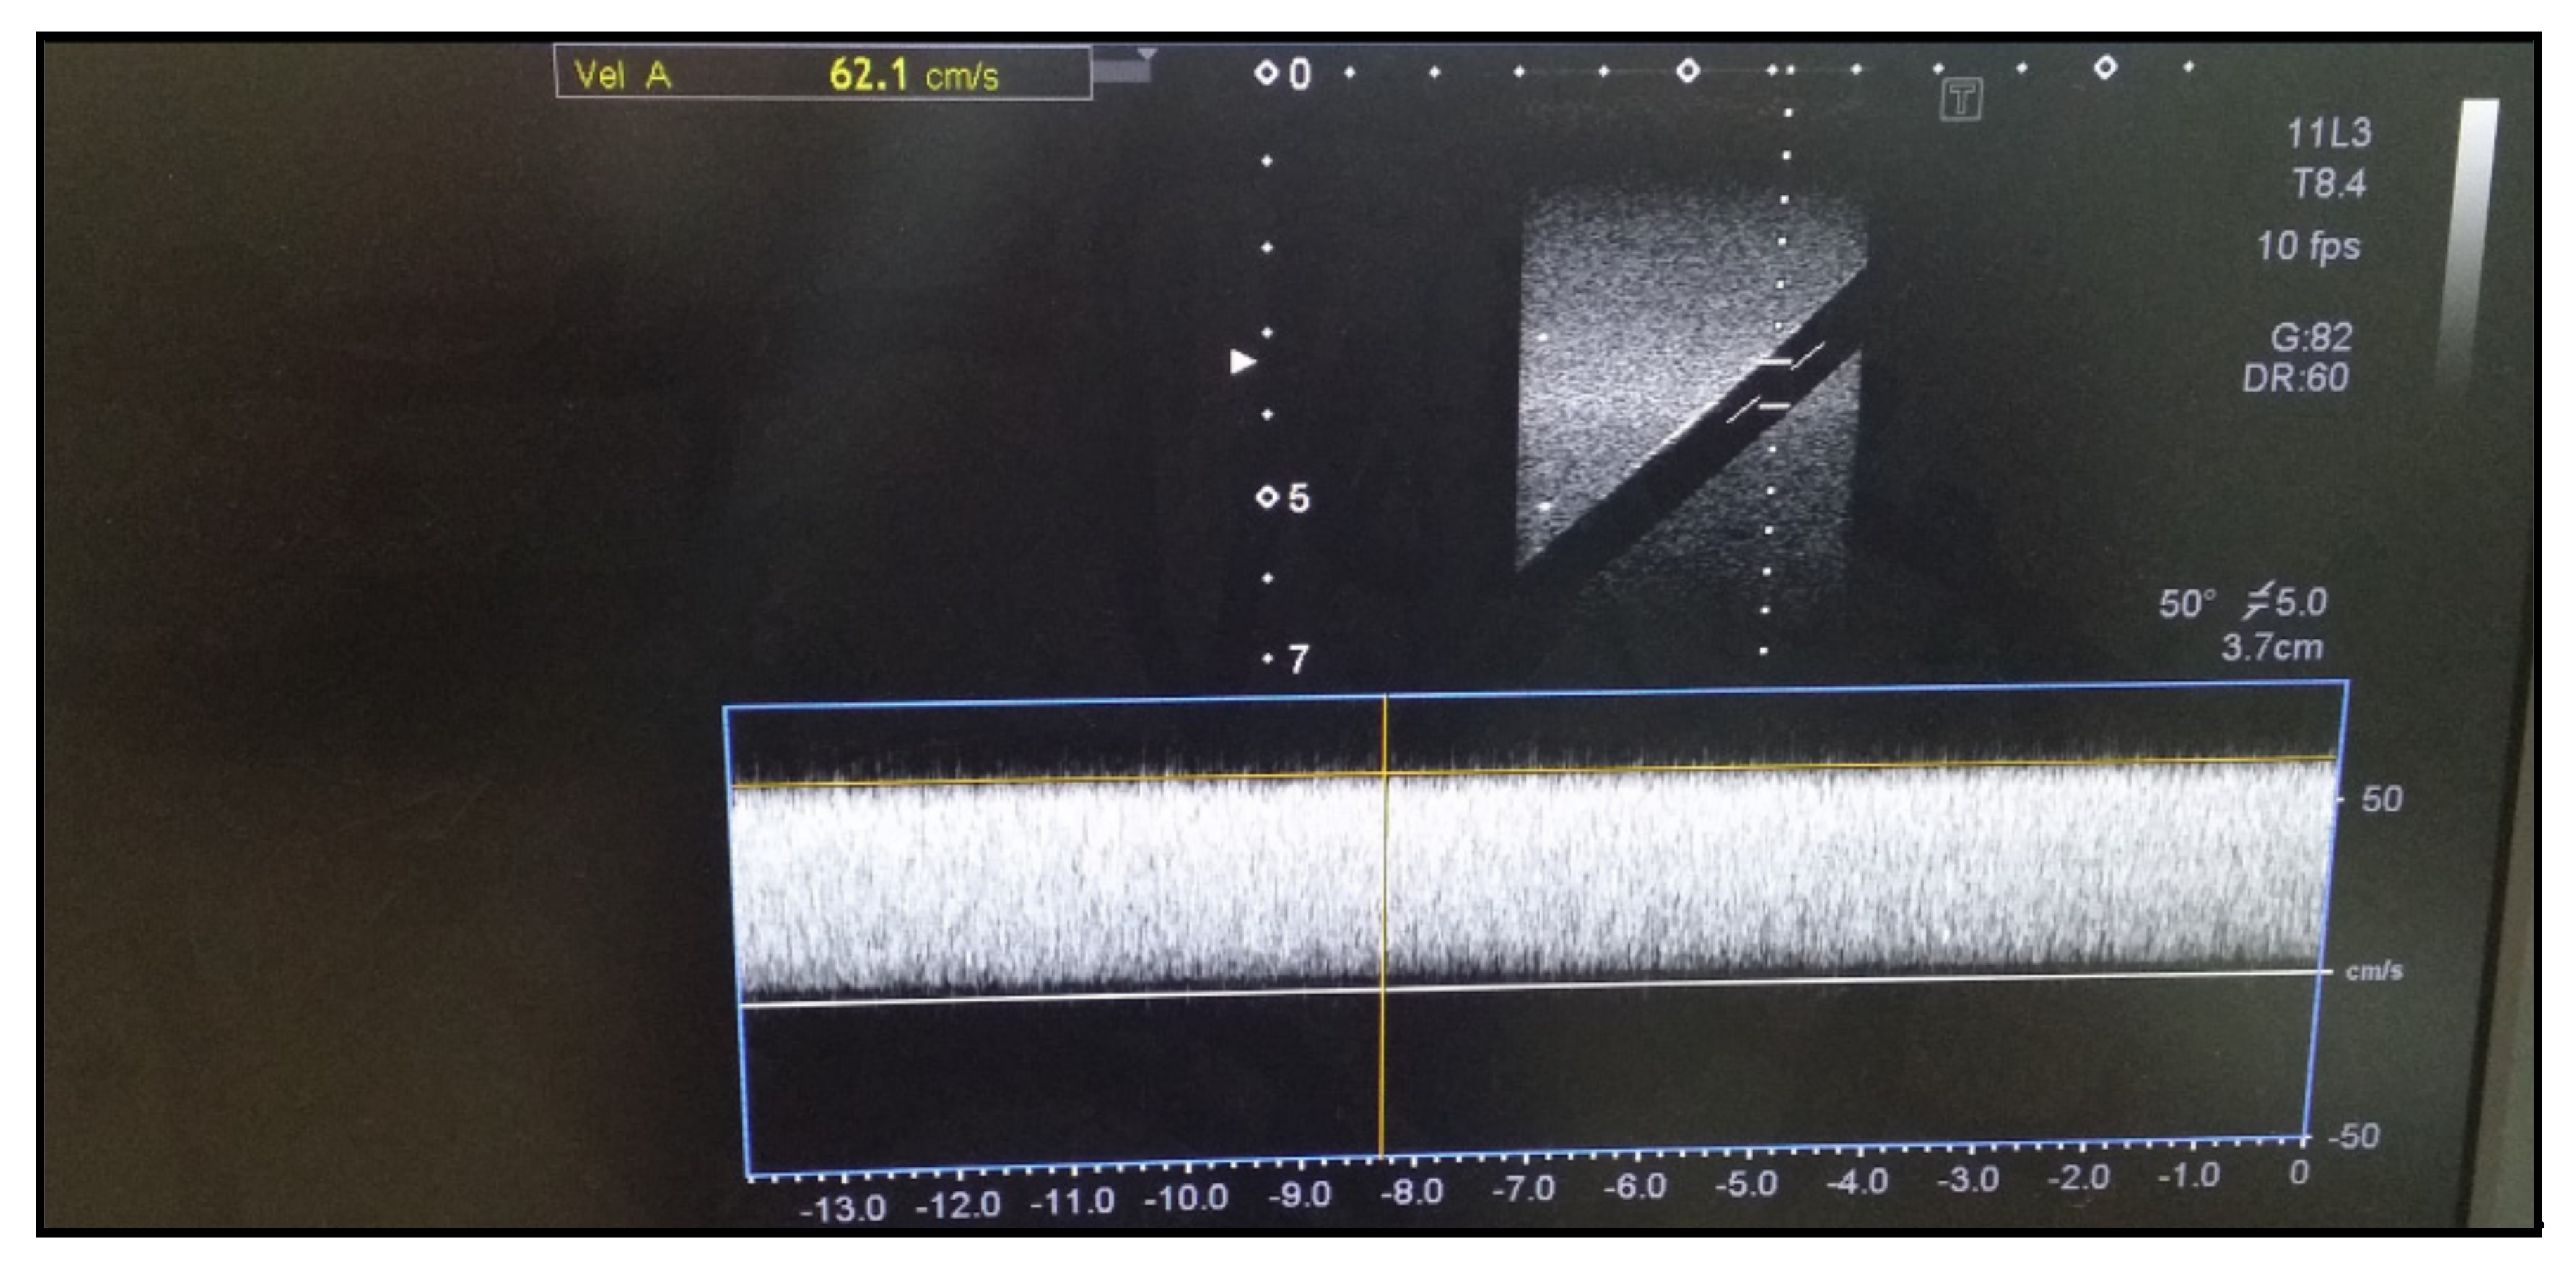

The accuracy test for blood flow velocity is performed if an ultrasound device has the D-mode function. The transducer in diagnostic ultrasound is brought into contact with the flow rate simulator to measure the flow velocity using the D-mode. The vertical axis represents velocity (cm/s). The accuracy test should be performed within 15% of the reference value (60 cm/s). As shown in Figure 7, we tested with a reference value for flow velocity of 60 cm/s and obtained a blood flow velocity of 62.1 cm/s with an error rate of less than 15%.

Figure 7. Blood flow accuracy.